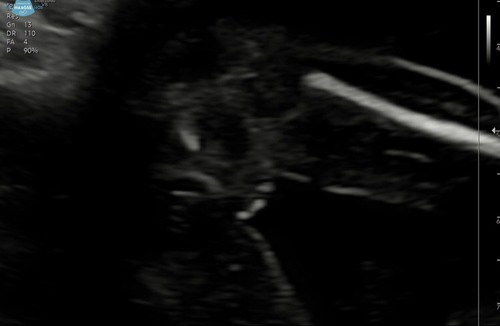

Ik heb nog een foto die hebben ze me via een link gestuurd.misschien is het daarop beter te zien